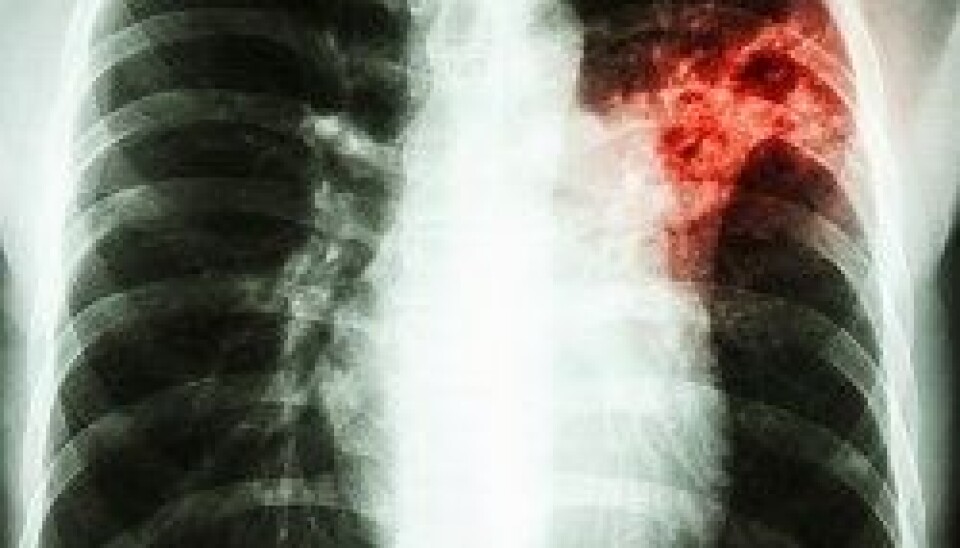

Tuberkulose tok over 1,2 millioner liv i 2023

Omtrent 1,25 millioner mennesker døde av tuberkulose i fjor. Det er dermed den smittefarlige sykdommen som krevde flest liv i 2023, ifølge WHO.